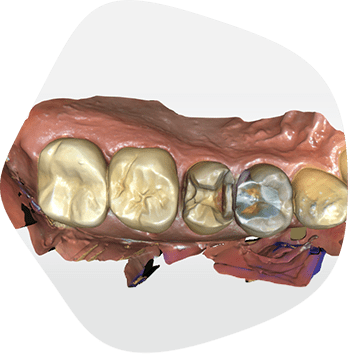

当院の虫歯治療

診療メニューには、虫歯治療、歯周病治療、インプラント治療、詰め物・被せ物、入れ歯治療、口腔外科、予防歯科、

メタルフリー治療、ホワイトニングなどがあります。